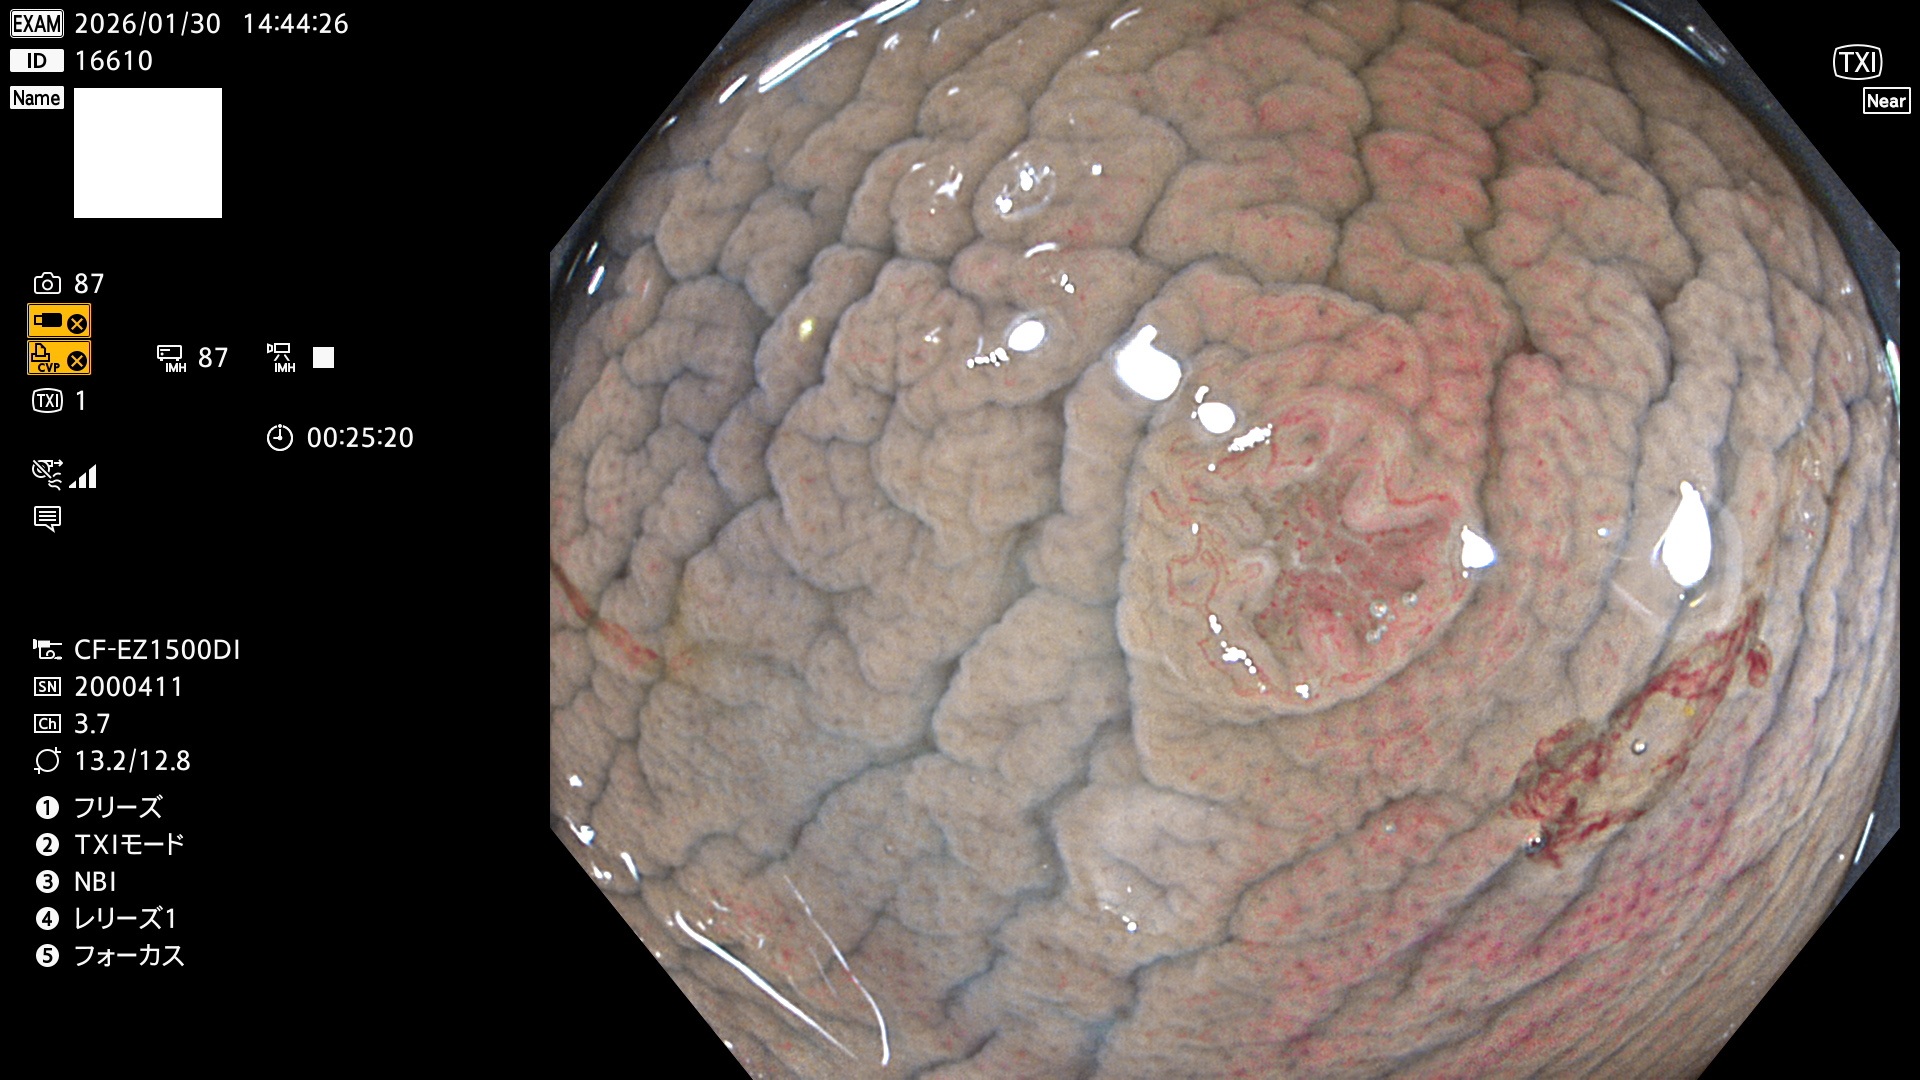

完全に平坦な物をUb、陥凹している物をUcと呼びます。Ubは認識が困難で、Ucはびらん(炎症)と紛らわしいために見落とされやすく、「内視鏡後・大腸癌」の原因になります。

毎週の検査(木・金・土・日)に発見されたUbとUc型・腺腫を、その週の日曜の夜にUPし1週間、提示します。

2026年1月29日〜2月1日の4日間(40件)10個 (Uc_ADR=10個/40人=25%)